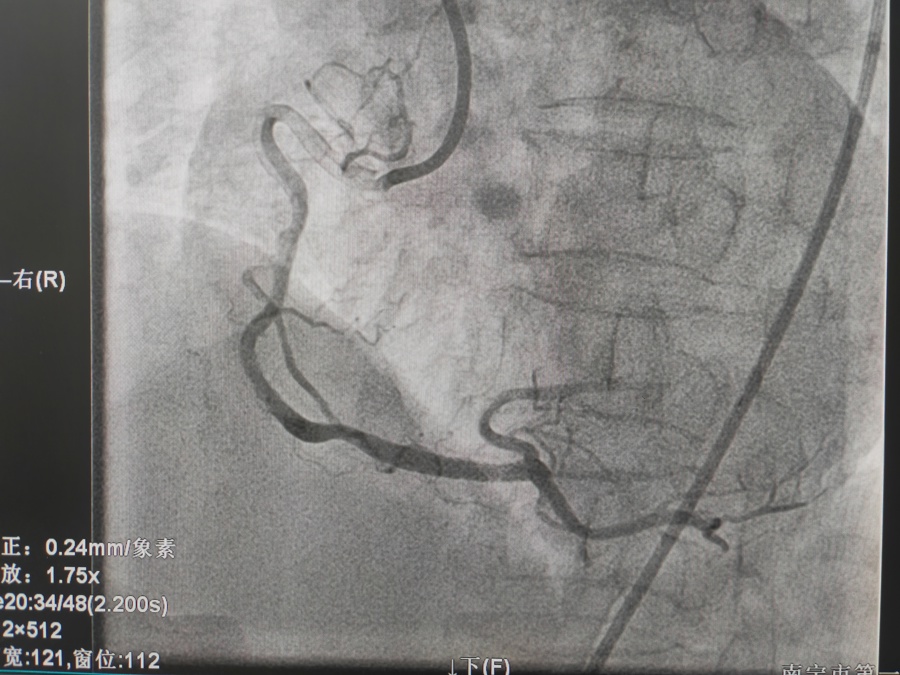

冠心病的治疗

冠脉支架置入术是将以不锈钢或合金材料刻制或绕制成管状而其管壁星网状带有间隙的支架(药物支架),置入冠状动脉内已经或未经PTCA扩张的狭容节段支撑血管壁,维持血流畅通。因球囊扩张后,约20-40%的病变会发生再狭窄,有些会发生急性冠脉闭塞而导致急性心肌梗死或死亡,所以在扩张后,多致需要再用冠脉内支架将病变处永久性撑开,即支架置入。置入支架是为了减少斑块撕袭后塌陷,急性塞,增加手术安全性,减少再狭窄。目前PTCA加上支架置入术已成为治疗冠心病的重要手段。